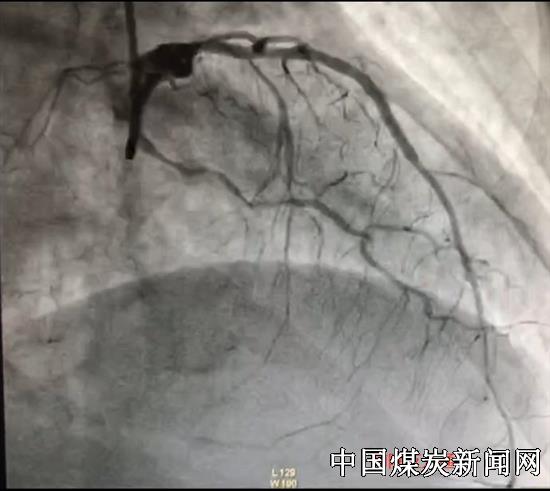

6月29日,51岁女性患者,因胸痛难忍来医院急诊。经诊断患者为陈旧性心肌梗塞(前降支慢性闭塞病变) 不稳定心绞痛(右冠开口病变)合并心功能不全,冠脉造影提示前降支近中段完全闭塞,远端可因侧支循环显影,右冠开口次全闭塞,回旋支远段亦完全闭塞,此为临床上所说的三支病变。这种病变首选的治疗手段是心脏搭桥手术,心脏搭桥手术又称冠状动脉旁路移植术通常在全身麻醉的情况下进行,需要开胸,手术时间长,创伤大,患者及家属考虑后不接受冠脉搭桥,要求尝试冠脉介入治疗。他们将希望及生命交给了心内科。心内科介入团队在赵军峰主任的指导下,尹威医师凭着丰富的手术经验及高超的专业素质,在与魏鹏辉医师的密切配合下,仅用两根导丝和娴熟的手法将前降血管打通并成功植入支架,使前降支再次重建,极大改善病人心功能,同时处理了右冠的开口次全闭塞病变,整个CTO手术过程仅用了两个多小时。此手术的技术难度在心脏介入治疗领域走在了当地先进行列!术后得到了患者及家属的高度认可及赞扬!